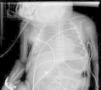

He was intubated after birth and received synchronized conventional mechanical ventilation from the 2nd minute of life. He needed surfactant administration three times, because of severe respiratory distress syndrome (RDS). On day (D) two of life he presented a pulmonary hemorrhage. On D17 he was moved from SIPPV+ volume guarantee (maximum settings: InspP=24cmH2O; frequency=60min–1; PEEP=5cmH2O; FiO2=0.6; VG=6.5ml/kg) to high frequency oscillatory ventilation (maximum settings: MAP=18; DeltaP=38; iT=33%; Freq=15Hz; FiO2=1). Blood cultures were negative as was reactive C protein. A 10 days course of systemic dexamethasone was started. Large cystic pneumatoceles appeared in the right and left lower lobe on D19 (Figs. 1 and 2). Taking a wait and see attitude, the pneumotoceles spontaneously regressed on D32 (Fig. 3).2 Serial cultures of tracheal aspirates from D15 became positive for an extended-spectrum beta-lactamase (ESBL) Klebsiella pneumonia strain, only sensitive to amikacin.